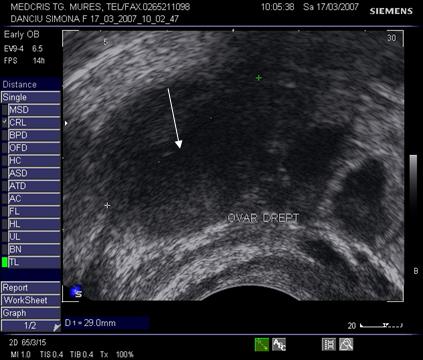

Fig nr.10. Corp galben( cu sageata ) in ovarul drept la o sarcina de 5 sapt, eco transvaginala